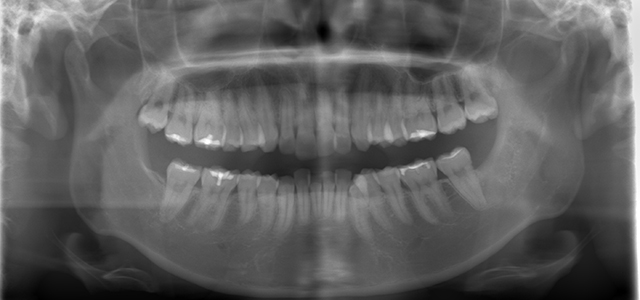

矯正前 パノラマX線

主訴 口元の突出感を治したい。ガミースマイルを治したい。

年齢 20代

治療法 上下顎マルチブラケット装置

抜歯の有無 上顎左右側第一小臼歯、下顎左右側第一小臼歯

治療期間 1年10ヶ月